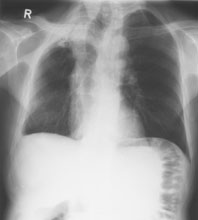

Ein 71-jähriger Italiener beklagt sich über einen reduzierten Allgemeinzustand und subfebrile Temperaturen. Er raucht seit 45 Jahren.

Husten und Auswurf hätte er immer gehabt, berichtet der Patient. Mit der Frage nach einem Infiltrat wird ein Röntgenbild verordnet:

Thorax pa

Bild vergrössern

Frage 1

Welche Befunde imponieren (mehrere richtige Antworten möglich)?